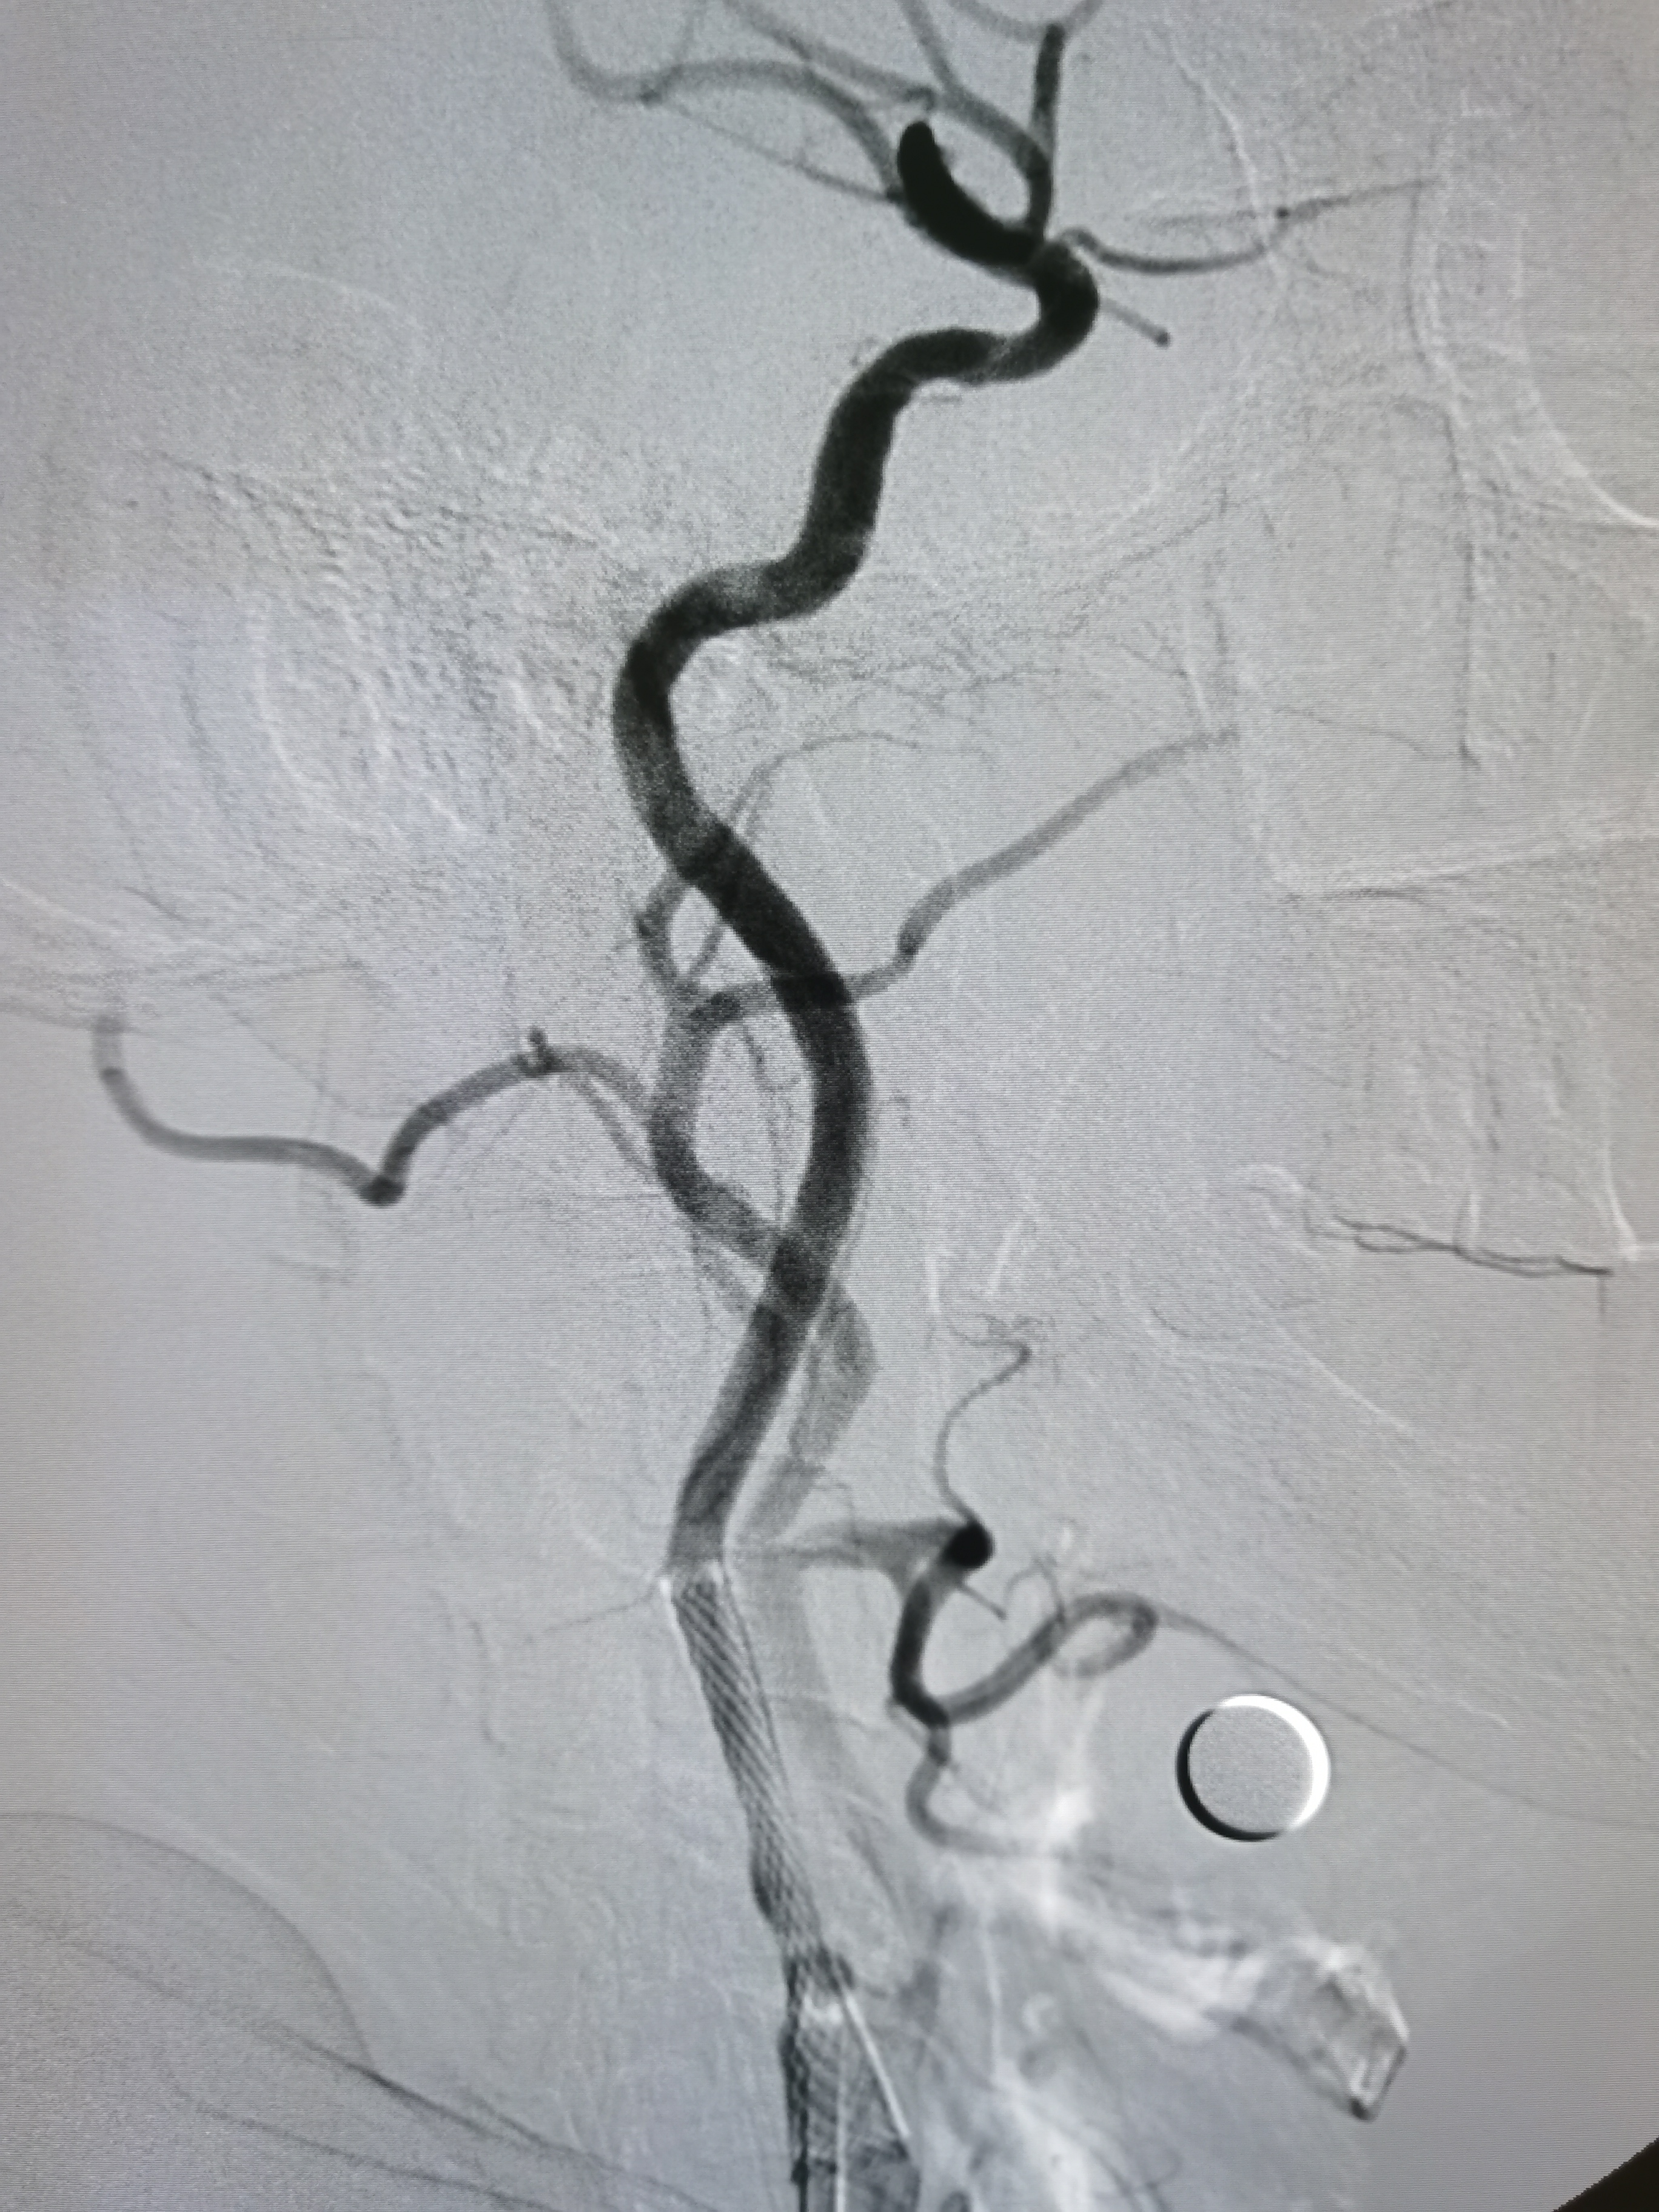

支架释放后狭窄解除。

支架释放后颅内血供改善。

颅内血供良好。